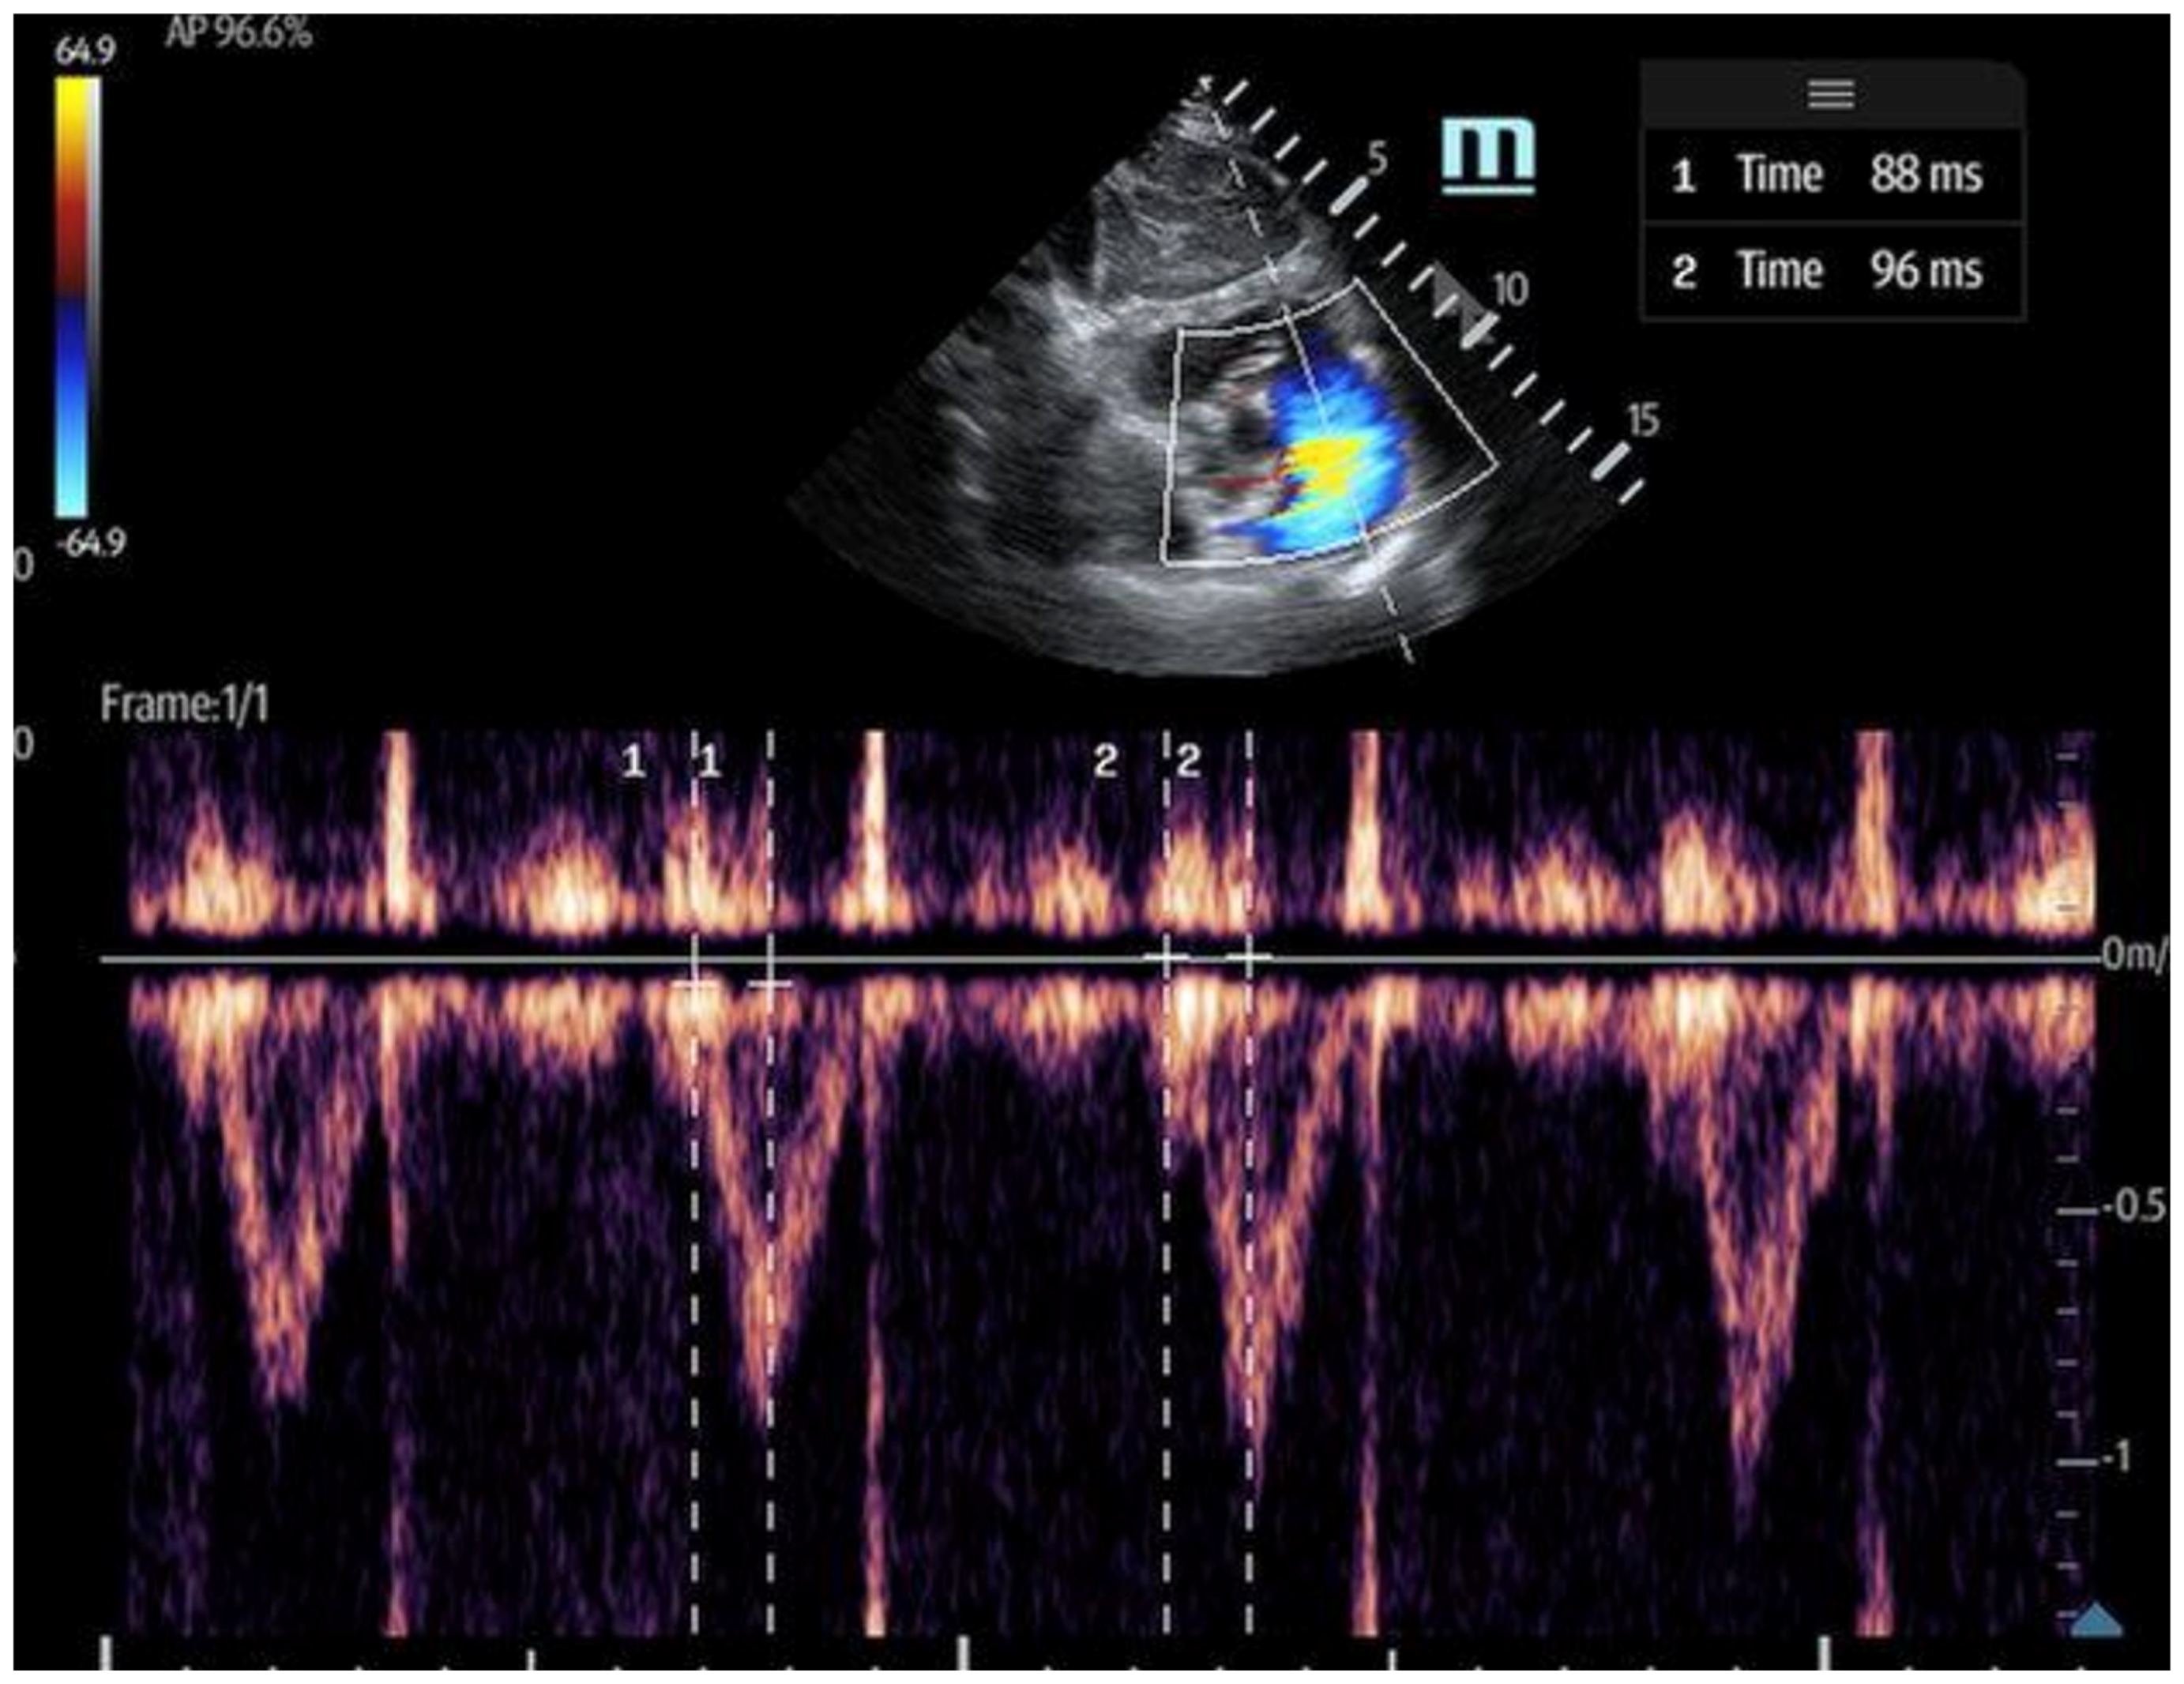

3. Venous excess ultrasound (VExUS): This has emerged as a valuable adjunct to IVC measurements in evaluating volume-overloaded states, utilizing pulse-wave (PW) Doppler to assess hepatic, portal, and intrarenal venous flow [23] (Figure 3). This technique provides direct insight into peripheral venous congestion and organ dysfunction, with a scoring that incorporates the IVC diameter to grade congestion severity [16] (Figure 4).

Figure 3.

Venous congestion evaluation using the ultrasound (VExUS) protocol for ultrasound scanning [24].

Pulse-wave Doppler identifies flow moving towards the transducer and positive deflections and flow moving away as negative, with the amplitude representing speed [16]. Normal venous flow varies by location and is influenced by right atrial pressure (RAP), venous compliance, and distance from the heart. Hepatic vein flow is pulsatile, reflecting RAP variations during systole and diastole due to its direct connection with the IVC. In contrast, flow in more distal intrarenal veins is continuous and no longer reflects RAP [16]. The portal vein, which reflects the portal circulation, also exhibits continuous flow unaffected by RAP. As the RAP increases, pressure changes are transmitted to these peripheral organ veins, altering flow and impacting organ function.